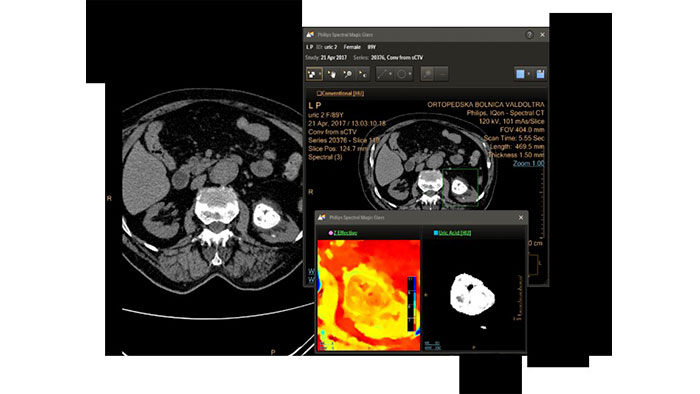

IQon Spectral CT Functionality

IQon Spectral CT is the only scanner to offer CT Spectral Light Magic Glass and CT Spectral Magic Glass on PACS, helping radiologists review and analyze multiple layers of spectral data at once, including on their PACS.

Benefits

IQon Spectral CT* Functionality

The spectral viewer is optimized for analysis of spectral data sets from the IQon Spectral CT Scanner. Obtain a comprehensive overview of each patient quickly and easily, quantify quickly, and assist in diagnosis. It is designed to accommodate general spectral viewing needs with additional tools to assist in CT images analysis.

* IQon CT reconstruction provides a single DICOM entity containing sufficient information for retrospective analysis - Spectral Base Image (SBI). SBI contains all the spectrum of spectral results with no need for additional reconstruction or post-processing. Spectral applications are creating different spectral results from SBI.